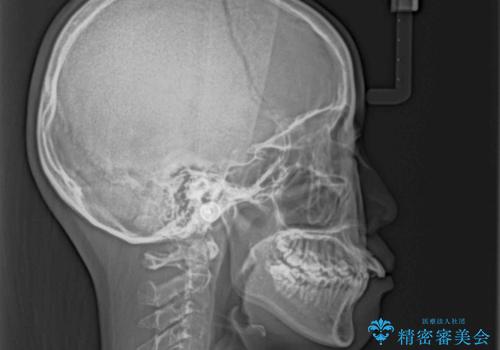

口元を積極的に引っ込めるために、上下左右の小臼歯計4本を抜歯することとしました。

舌の突出癖が強いため、しっかりと口元を引っ込めるため、舌のトレーニングをしっかりと行いながら矯正治療を行うこととしました。